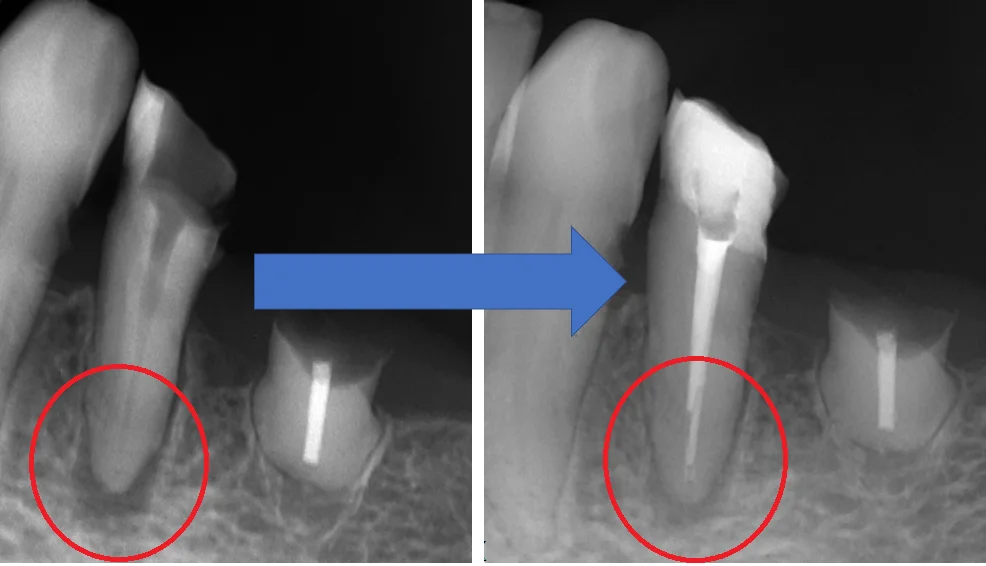

術前術後の写真がこちらです。

比較してみると、根の先の膿が溜まっている部分に少し骨が出来てきており、治癒傾向にあることが分かります。